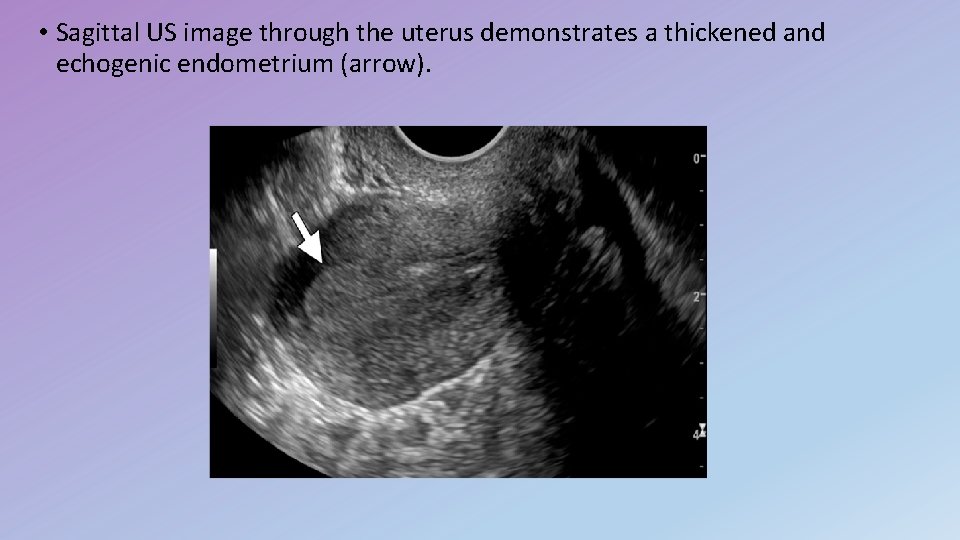

• Sagittal US image through the uterus demonstrates a thickened and echogenic endometrium (arrow).